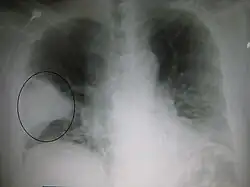

Pleural abnormalities

Fluid in space between the lung and the chest wall is termed a pleural effusion. There needs to be at least 75 mL of pleural fluid in order to blunt the costophrenic angle on the lateral chest radiograph and 200 mL of pleural fluid in order to blunt the costophrenic angle on the posteroanterior chest radiograph. On a lateral decubitus, amounts as small as 50ml of fluid are possible. Pleural effusions typically have a meniscus visible on an erect chest radiograph, but loculated effusions (as occur with an empyema) may have a lenticular shape (the fluid making an obtuse angle with the chest wall).

Pleural thickening may cause blunting of the costophrenic angle, but is distinguished from pleural fluid by the fact that it occurs as a linear shadow ascending vertically and clinging to the ribs.